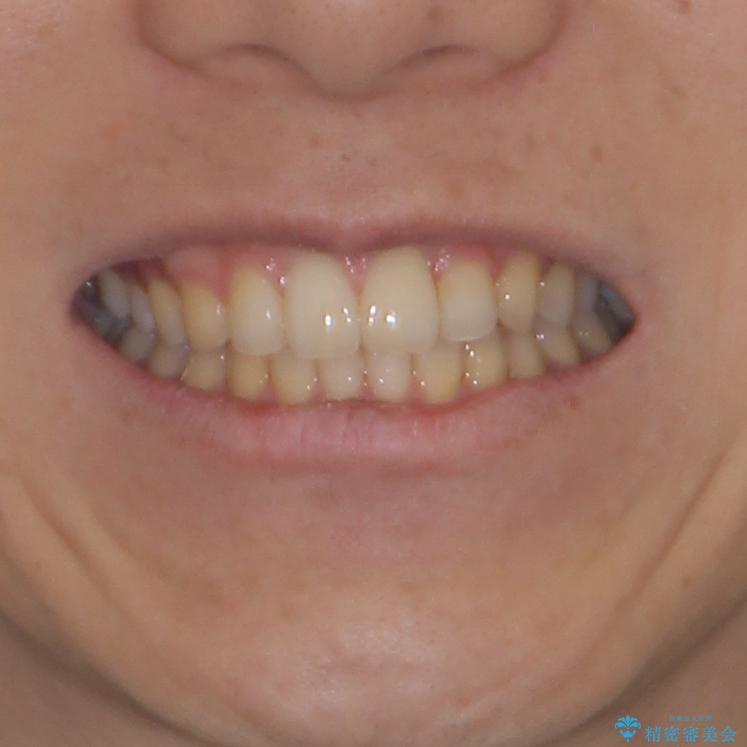

前歯のクロスバイトと抜歯が必要な奥歯の虫歯 インビザラインとインプラント治療

- 前歯のクロスバイトと、大学生のころから放置している虫歯を気にして来院された患者様です。

マウスピースでの矯正治療を希望されていましたが、前歯のクロスバイトは不十分な仕上がりや歯髄壊死などのリスクが高くなるため、術前にワイヤーで大まかに整えてからインビザラインにて矯正治療を行うこととしました。